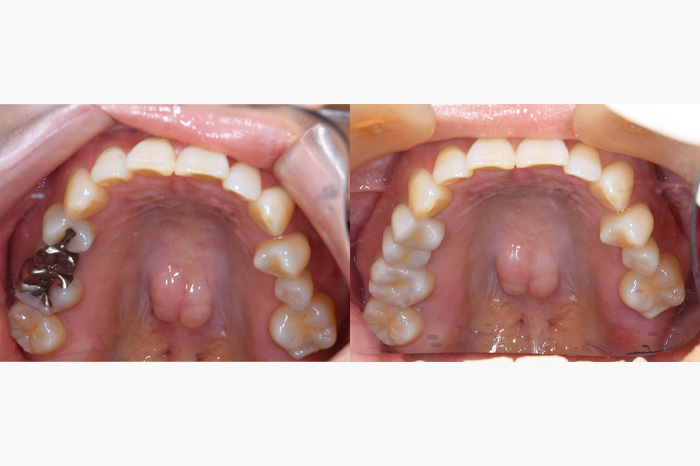

全顎のケース

銀歯を全部外してセラミックの詰め物、被せ物にしたケースになります。銀歯の中では虫歯になっている事が多く、よく私もそういうケースを目にします。こちらのケースでは、虫歯が大きくなっており、残せない歯があったため、インプラントを使用している部分もあります。

また、銀歯があると金属アレルギーを発症しやすくなったり、ひどくなると掌蹠膿疱症といって、手足がかゆくなったりすることもあります。金属アレルギーがある方は早めに金属の歯を外して、金属アレルギーと関係のない詰め物や被せ物を入れることをお勧めいたします。

| 年齢 | 50代・男性 |

|---|---|

| 主訴 | 銀歯をやりかえたい |

| 治療内容 | 左下の奥歯に歯がありませんでしたのでインプラントを行います。また気にされていた銀歯をすべてセラミックでやり直しました。 また、上の前歯に入っていた被せ物も一部歯にフィットしていない部分もありましたのであたらしく作成しました。 |

| 治療費 | ジルコニアボンドクラウン 11本: 合計1,815,000円(税込) (165,000円×11本) ジルコニアステインクラウン 6本: 合計660,000円(税込) (110,000円×6本) インプラント 1本: 合計539,000円(税込) セラミックインレー 5本: 合計275,000円(税込) (55,000円×5本) |

| 治療期間 | 6ヶ月 |

| リスク・副作用 | 全顎にわたる治療は噛み合わせが重要なため期間がかかります。 インレー、クラウンセット後にしみるといった症状がおこることが あります。 インレー、クラウンセット後に痛みがでて神経をとらないといけなく なることがあります。 |